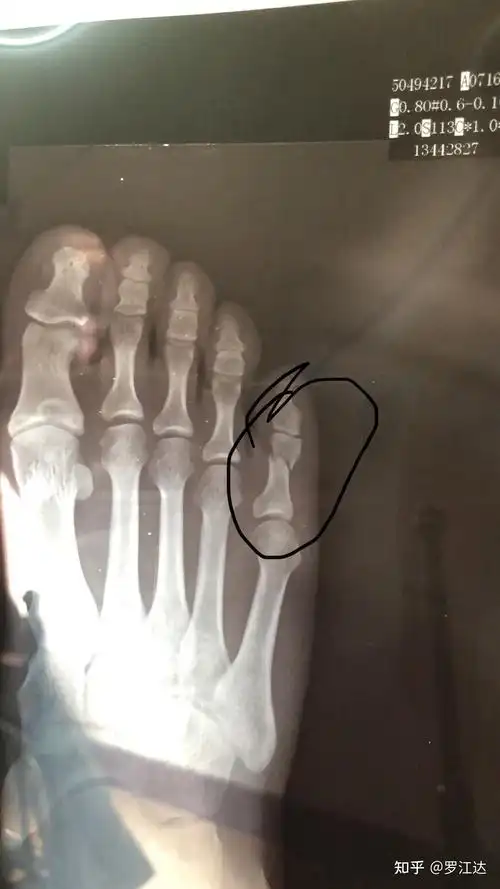

第五趾骨基底部骨折第40天

第五跖骨基底部骨折,没打石膏,用护具,但因天热不是时刻都带着,小脚趾